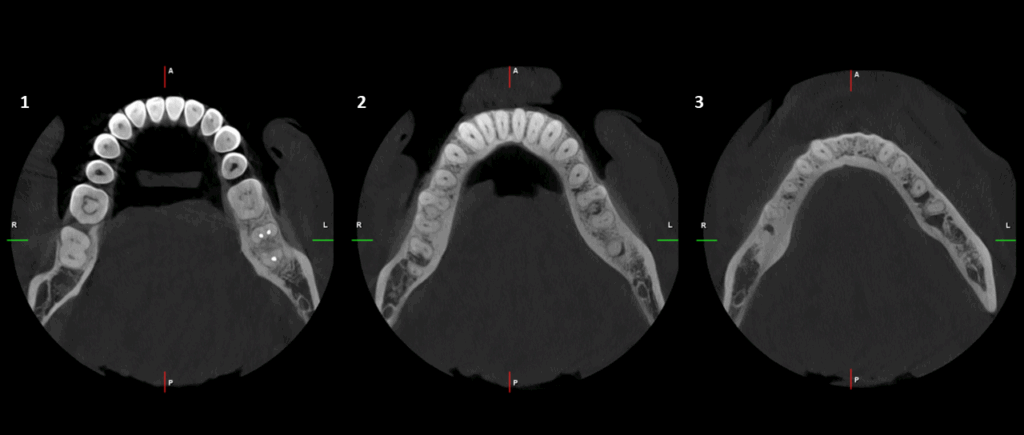

En el estudio complementario mediante tomografía computarizada de haz cónico (TCHC), se observa la obturación subextendida de conductos en la raíz mesial de la pieza 37, se confirma el proceso osteolítico periapical y el aumento de la densidad ósea circundante con extensión hacia el conducto dentario inferior. En la pieza 46 se observa una restauración oclusal hiperdensa con material restaurador isodenso subyacente próximo a cámara pulpar y se corrobora el aumento de la densidad ósea periapical que además se extiende hacia la tabla ósea lingual.

CORTES AXIALES

- Osteítis condensante en piezas 37 y 46.